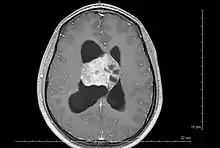

| Axial T1-weighted gadolinium-enhanced MRI image showing an enhancing mass with cystic changes consistent with central neurocytoma in the right lateral ventricle. | |